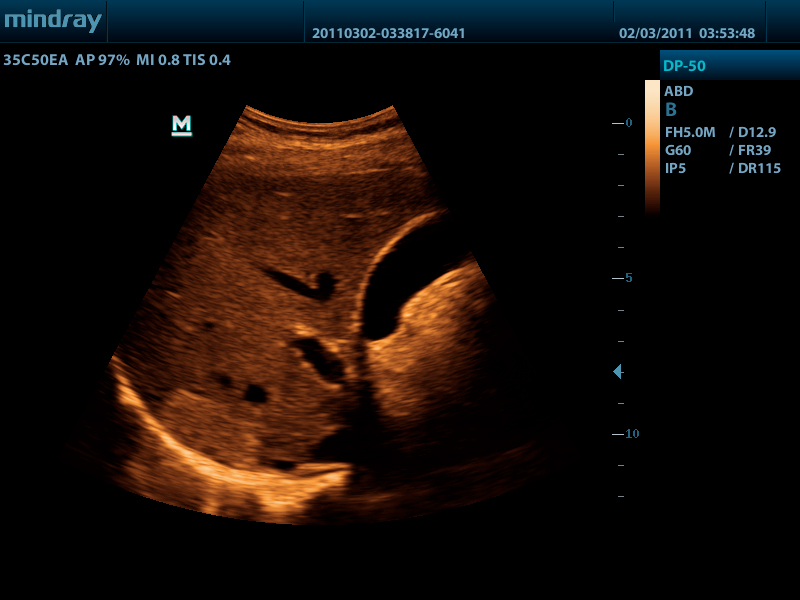

Портативный ультразвуковой сканер Mindray DP-50

Mindray DP-50 – портативная цифровая ультразвуковая система с ЖК монитором 15 дюймов (1024Х768)

и встроенными аккумуляторными батареями (опция) позволяющими работать в автономном режиме до 2-х часов.

Достоинства Mindray DP-50:

- карты колоризации (псевдоокрашивание).

DP-50 – портативный УЗИ сканер разработан на базе новой платформы X-treme engine, используемой в хорошо зарекомендовавших себя цветных сканерах с доплером моделей DC-3, DC-7, DC-6. Эта платформа открывает возможности для расширений до уровня цветных сканеров и совместимости с широким диапазоном периферийного оборудования. X-treme означает интеллект, высокую скорость обработки данных, многоуровневую передачу сигналов, а также возможность оптимизации изображения и модульного расширения.

Качество изображения:

- iBeam: функция улучшения разрешающей способности изображения

- iClear: функция подавления шумов на изображении для улучшения детализации и контрастности изображения

- изображение на основе гармоник с фазовым сдвигом

- трапецевидное изображение, псевдоокрашивание и B Steer

Применяемые датчики DP-50:

Конвексный датчик 35C50EA (2.0/3.5/4.5/5.0/Н5.0/Н6.0) R50